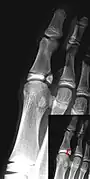

Salter–Harris IV fracture of big toe proximal phalanx.